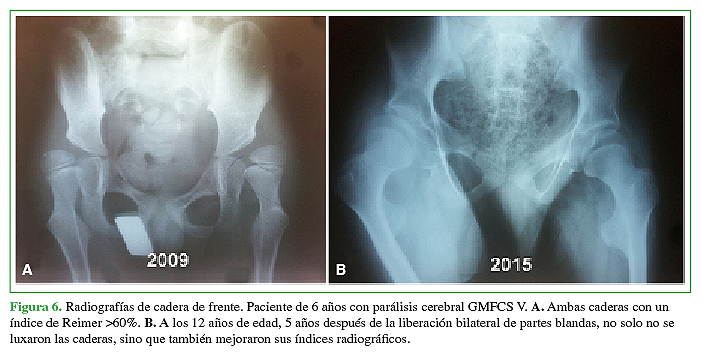

PropiaConsiderando el IR y su efecto en la prevención de cirugías óseas, los resultados fueron: serie A: 55% buenos, 25% regulares, 15% pobres y 5% fracaso; serie B: 50% buenos, 31% regulares, 13% pobres y 6% fracaso (p 0,1, diferencia no significativa) (Figuras 5 y 6).

A. Ambas caderas con uníndice de Reimer >60%. B. A los 12 años de edad, 5 años después de la liberación bilateral de partes blandas, no solo no se luxaron las caderas, sino que también mejoraron sus índices radiográficos.